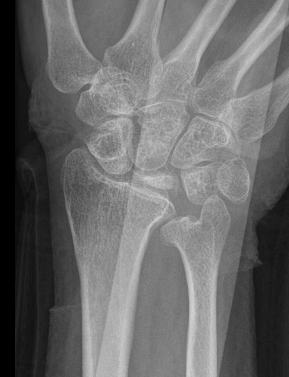

| Stage IIIB | Stage IV |

|---|---|

|

Collapse / fragmentation Scaphoid flexed / Capitate migrates proximally |

Pancarpal osteoarthritis |

![]() |